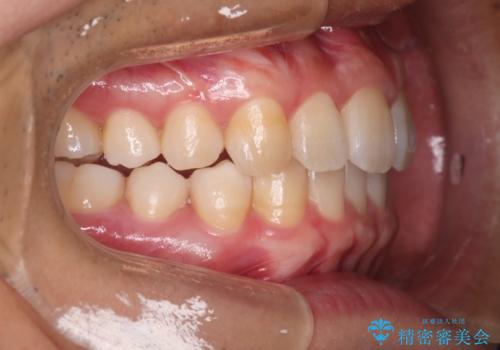

上の前歯が出ているという主訴が綺麗に改善されました。

その他の部位のがたつき、奥歯の噛み合わせも以前と比べると良くなっています。

目立たない装置で治療期間も10ヶ月と短く終了することができました。